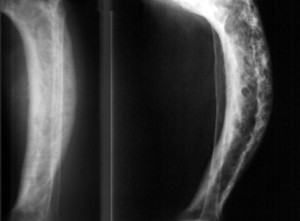

Остеопороз может быть выражен двумя типами: пятнистый и равномерный. В обоих случаях будет наблюдаться повышенная прозрачность костных узоров. Пятнистый остеопороз отличается очаговыми группами просветов на фоне структурного рисунка костной ткани. При равномерном варианте просветы имеют однородный диффузный характер. Запущенный остеохондроз приводит к тому, что кость на рентгене практически не видно – она становится слишком проницаема для изучения.

Пятнистый и равномерный остеопороз не имеют принципиальных различий. Как правило, пятнистый тип выражает ранний патологический процесс, принимая затем равномерную форму.